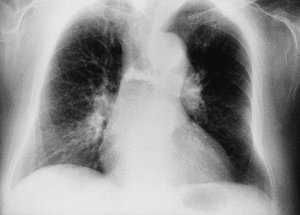

En la radiografía posteroanterior y lateral de tórax observamos como hallazgo más significativo una disminución de la altura y aumento de densidad de un cuerpo vertebral dorsal medio.

Fig. 1.

En esta paciente, coincidiendo con el dolor, se realiza radiografía dorsal donde se aprecia aplastamiento D5-D8. Posteriormente en la resonancia magnética se demuestra fractura y aplastamiento reciente de D7 en probable relación con la osteoporosis que presenta. Se le realizó una vertebroplastia mejorando clínicamente en el plazo de varios días.